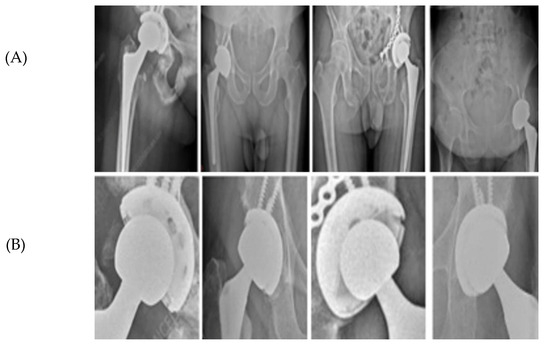

Figure 3.

ROI extraction from hip prosthesis X-rays. (A) AP pelvic radiographs containing a hip prosthesis. (B) Automatically extracted Regions of Interest (ROIs) generated by the YOLOv5 localization stage. Each ROI corresponds to the model’s predicted implant region and is forwarded to the subsequent edge-based refinement and circle-fitting pipeline (RANSAC and Hough-based detection). This step ensures that only implant-focused, anatomically relevant regions are processed during circle estimation.

This ROI is subsequently cropped at full resolution and passed to the circle-refinement pipeline (Section E), where component-level delineation is performed. Within the ROI, candidate femoral head and AC circles are generated using RANSAC-based fitting, with a Hough-transform fallback for cases of insufficient edge continuity. All candidates are then subjected to Canny-based edge validation and anatomically constrained filtering to ensure geometrically and biomechanically plausible selection of the final two circles. In this framework, the ROI serves purely as a spatial prior that restricts the search space, while the accurate identification of the femoral head and AC is achieved exclusively through the model’s geometric refinement stages.

Figure 5 provides a qualitative illustration of the proposed framework on real hip prosthesis radiographs from the external test dataset.

Figure 5.

Femoral and AC Circle Detection Outputs on Hip Prosthesis X-ray Images. (A) shows the original X-ray images, highlighting the variability in implant designs, image quality, and anatomical configurations. (B) presents the intermediate detection results obtained using the YOLOv5-based ROI localization, where coarse circular estimations of the femoral head and acetabular cup are generated. These initial predictions successfully isolate the relevant regions despite challenging conditions such as metallic screws, projection differences, pelvic asymmetry, and partial occlusion of the acetabular rim. (C) displays the final refined circle detections after applying the geometric processing pipeline, including edge detection, Edge-Snap refinement, and RANSAC-based circle fitting. The resulting femoral-head and acetabular cup circles exhibit stable center positions and consistent radii across all examples.

The qualitative results demonstrate the robustness and reliability of the proposed hybrid approach in accurately identifying circular prosthetic components across heterogeneous radiographic conditions. All radiographs shown were exclusively used for testing and were not included in the training or validation stages, confirming the generalization capability of the proposed framework.